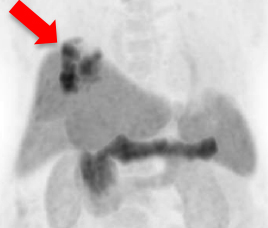

氟18 PSMA正电子/电脑双融扫描显示大部分病灶於鑥177 PSMA放射核素治疗後可见改善(红色箭头所示)。

治疗後扫描显示病灶活跃度大大降低。